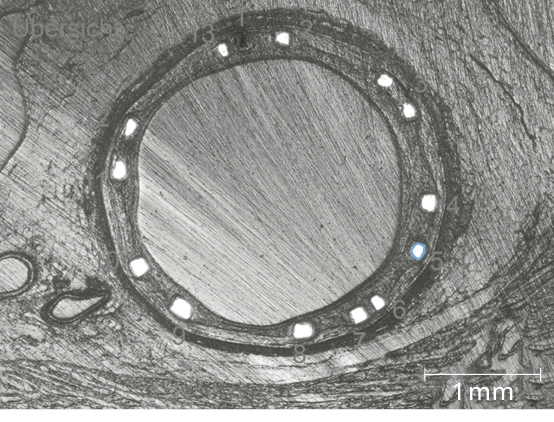

Predictable, homogeneous resorption process6

Equal resorption between struts6

Uniform shape due to homogeneous strut resorption6

More than 3 months vessel support6,7

>99% of struts no longer visible at 12 months8